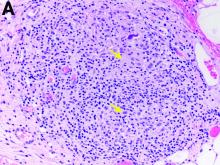

The gallbladder (Figure B) as well as the intraoperative liver biopsy (Figure C; insert showing cells under higher power) showed non-necrotizing granulomas along with scattered infiltration by atypical large cells morphologically consistent with Hodgkin-Reed-Sternberg cells in a lymphoid background (Figures B, C, green arrows). Immunohistochemistry showed these were positive for CD30 (Figure D, liver biopsy), weakly positive for PAX5, and negative for CD15, CD20, CD79a, and ALK-1. Given the pathologic findings, the patient was diagnosed with Hodgkins lymphoma.

The patient had a history of mediastinoscopy and lymph node biopsy in the past at an outside hospital with reported noncaseating granulomas and no other abnormalities; those slides could not be obtained for independent review. Primary lymphomas of the liver are exceedingly rare, but advanced lymphoma can have liver involvement.1 Hodgkins lymphoma of the liver is extremely uncommon.2 It can present with fever, hepatomegaly, and jaundice.1 The diagnostic yield of a liver biopsy ranges from 5% to 10% depending on core versus wedge biopsy.1 Pathologically, there is portal inflammation and atypical histiocytic aggregates but Hodgkin-Reed-Sternberg cells are required for diagnosis. These cells stain positive for CD15 and CD30 in around 80% of cases.3 Lymphoma should remain in the differential when granulomas are seen in the liver biopsy. Our patient clinically decompensated by the time the diagnosis was confirmed. The family decided not to pursue aggressive treatment in hospital and the patient was discharged home where she expired.